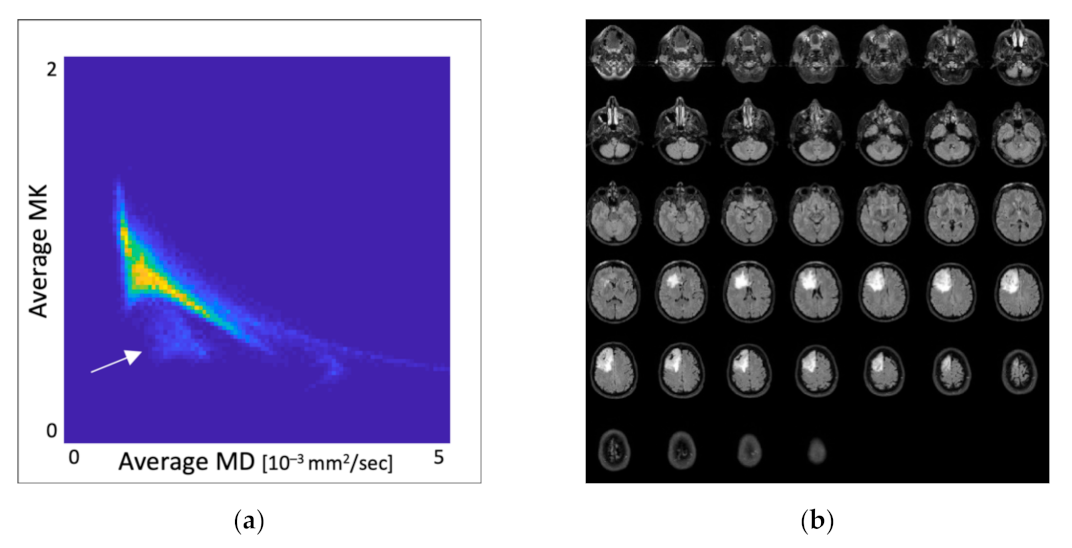

3.1. Distribution of MK and MD Values in Whole-Brain DKI Maps